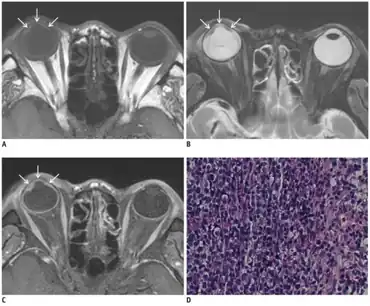

| a-c)Posttransplantation intraocular lymphoma- MR images showing smooth, undulating soft-tissue lesion in iris and anterior chamber d)photomicrograph consistent with diffuse large B-cell lymphoma | |